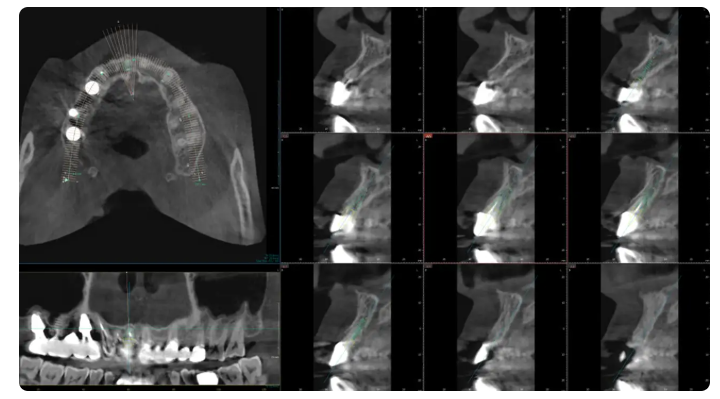

1️⃣어디까지 확인하고 시작하는지

먼저 뼈 상태나 잇몸 상태,

그리고 저작할 때 힘이 전달되는 방향까지

어디까지 살펴보고 시작하는지가 중요합니다.

✔왜 이 위치에 진행되는지 설명해 주는지

→ CT나 사진으로

직접 확인시켜주는지 살펴보세요.